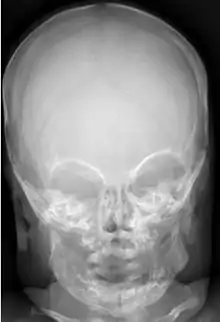

Radiographs initially show layers of periosteal new bone formation with cortical thickening. Periosteal new bone may cover the diaphysis of the bone, causing an increase in diameter of the bone. Over time, the periosteal new bone density increases, becoming homogenous with the underlying cortex. Eventually, the bone remodels and resumes a normal appearance.

Most infants with infantile cortical hyperostosis are diagnosed by physical examination. X-rays can confirm the presence of bone changes and soft tissue swelling. Biopsy of the affected areas can confirm the presence of typical histopathological changes. No specific blood tests exist, but tests such as erythrocyte sedimentation rate (ESR) and alkaline phosphatase levels are often elevated. A complete blood count may show anemia (low red blood cell count) and leukocytosis (high white blood cell count). Other tests may be done to help exclude other diagnoses. Ultrasound imaging can help diagnose prenatal cases.